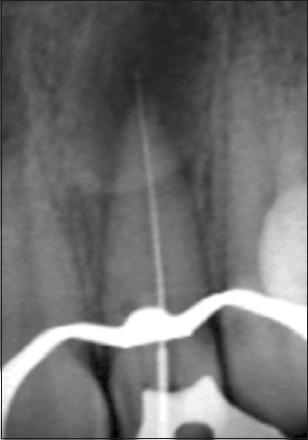

The integration of artificial intelligence in dentistry has seen remarkable advancements, especially in diagnostic imaging. This study evaluates and compares the accuracy of deep learning models with that of dental postgraduate students in determining working length on intraoral periapical radiographs.

One hundred anonymized radiographs of single-rooted teeth with files at working length were obtained. The images were preprocessed and used to train a deep learning model. Five dental postgraduates visually estimated the working length after receiving training. Pixel counting in image processing software provided the gold standard measurement. Accuracy comparisons were performed using a -test.

The deep learning model demonstrated significantly higher accuracy (85%) compared to human estimations (mean accuracy 75.4%). The -test yielded = 0.0374 ( < 0.05), rejecting the null hypothesis.